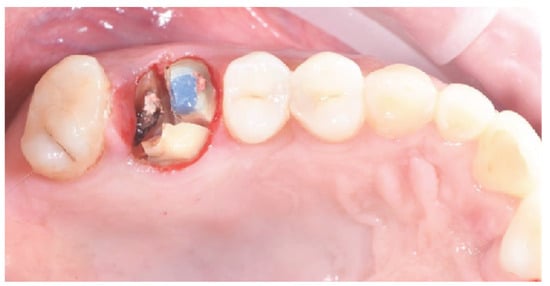

2.1. Socket Preservation Procedure

2.3. Biopsy Retrieval